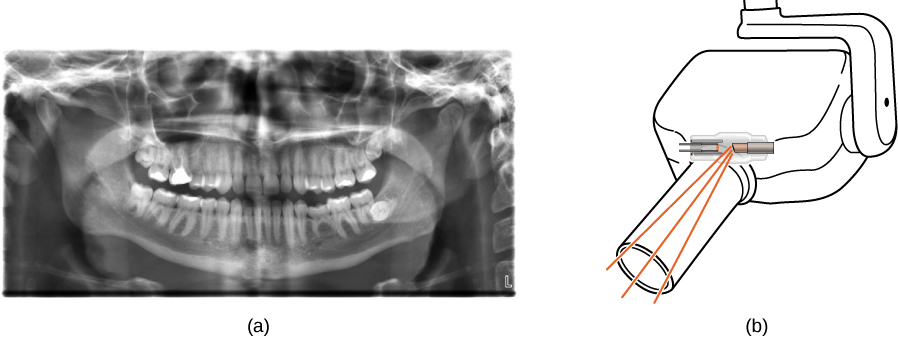

Figure (a) shows an X-ray image of front view of the jaw, especially the teeth. Figure (b) shows a drawing of an dental x ray machine.

Figure 8.25 (a) An X-ray image of a person’s teeth. (b) A typical X-ray machine in a dentist’s office produces relatively low-energy radiation to minimize patient exposure. (credit a: modification of work by “Dmitry G”/Wikimedia Commons)